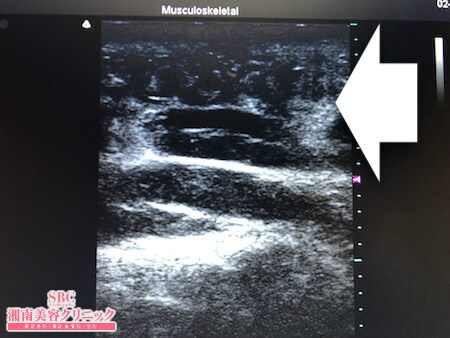

No.252642【脂肪吸引】コスプレでボディラインが出るお洋服を着るのでおなかの脂肪吸引を受ける!左腰術中タッチビュー